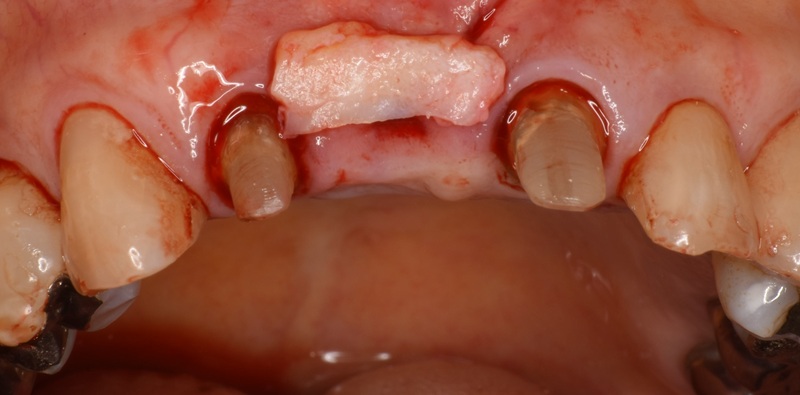

| 治療名 | 前歯のセラミックブリッジと結合組織移植術による審美修復症例 |

|---|---|

| 治療説明 |

古くなった前歯の被せ物の見た目を気にされ、ご相談いただきました。 その後、セラミックのブリッジを装着することで、天然歯のような自然な色味と形態を再現。見た目の美しさだけでなく、清掃性の高い健康的な歯ぐきを獲得することで、長期的な安定を図りました。 |

| 治療回数・期間 | 約3ヶ月 |

| 副作用とリスク | ・保険診療の銀歯に比べて費用が高額になり、治療期間も長くなることがあります。 ・結合組織移植術では、手術に伴う出血や腫れ、疼痛が生じる場合がありますが、多くは一時的です。 ・術後の腫れや違和感は数日〜1週間程度で落ち着くことが一般的です。 |

| 料金(税込) | セラミッククラウンブリッジ:396,000円 結合組織移植術:55,000円 合計:451,000円(税込) |